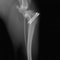

■ 症例20 ポメラニアン 8ヶ月 1.8kg

左右膝蓋骨脱臼 グレードⅢ

2ヶ月前から間欠的跛行が認められ、両膝の膝蓋骨脱臼整復術を行った。

手技は縫工筋及び内側広筋の解放、脛骨粗面の外側転位、滑車ブロック形造溝術、内外側関節包の縫縮を選択し実施した。

右側の膝蓋骨脱臼は上記手技で整復されたものの、左側はそれのみでは膝蓋骨が浮く様子が認められた。その為、PDS縫合糸にて膝蓋靱帯を1糸のみ縫合し、靱帯の縫縮を行った。

膝蓋骨脱臼は膝関節における膝蓋骨の内外側の脱臼と定義されるが、時として単純な内外の脱臼ではなく、膝蓋骨が大きく前方に浮き上がるように脱臼する場合がある。特にトイプードルやポメラニアンといった犬種に多く認められる。

内側脱臼に加えて前方への浮き上がりを矯正する為に、従来より脛骨粗面転移により膝蓋靭帯を外方と下方に引っ張り、固定する方法を選択する。膝蓋骨の前方への浮き上がりが軽度の場合は、従来法ではなく関節包の縫縮で対応していた。しかし、一部の症例で膝蓋骨の動きが悪くなり伸展機構が円滑に機能せずロボット様歩行になるケースがあった。

その為、膝蓋靭帯自体を縫縮する方法を採用した。この方法により、膝関節の伸展機構を妨げず膝蓋骨の軽度の浮きを矯正することが可能となった。

本症例の経過は良好である